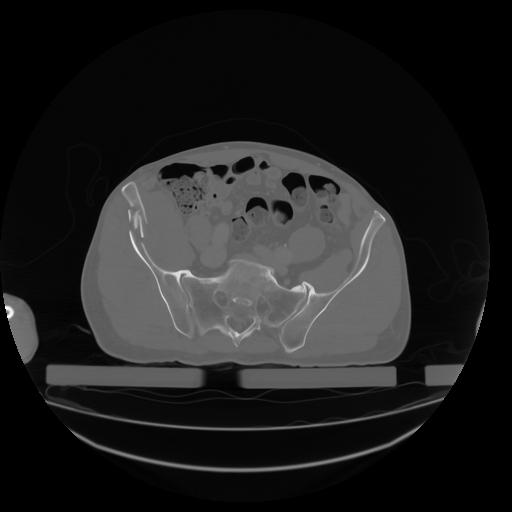

27 CUERPO,CE,Axial,3.0,CUERPO,,